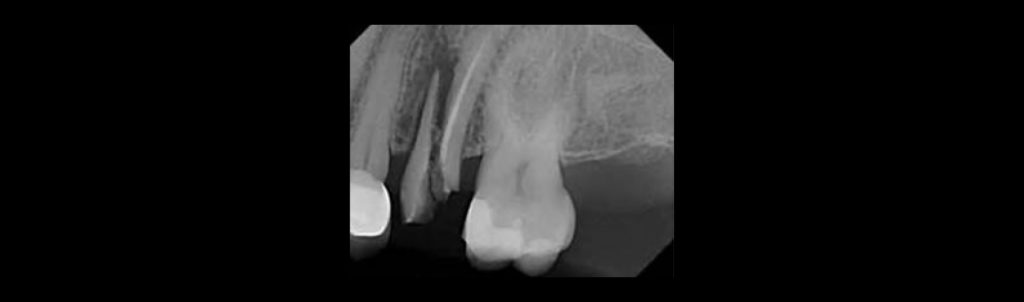

A thorough history and clinical exam form the basis of diagnosis. Percussion, palpation, periodontal assessment, pulp vitality testing, and visual inspection all contribute essential baseline data. Periapical radiographs help evaluate subgingival involvement, the extent of restoration, and periapical changes. Positive responses and the degree of tooth/root involvement will help determine the treatment pathway for cracked tooth syndrome.

Traditional radiographs rarely show cracks clearly, as most cracks run mesial–distal and cannot be captured by the X-ray beam. Attempting to image from multiple angles will not improve or enhance radiographic diagnosis.